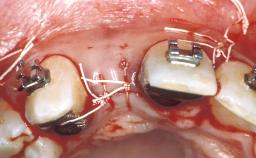

Surgical SAC classification

| Placement Protocol | - |

| Tooth Site | - |

| Socket Morphology | - |

| Socket Integrity | - |

| Bone Volume | - |

| Anatomic Risk | - |

| Esthetic Risk | - |